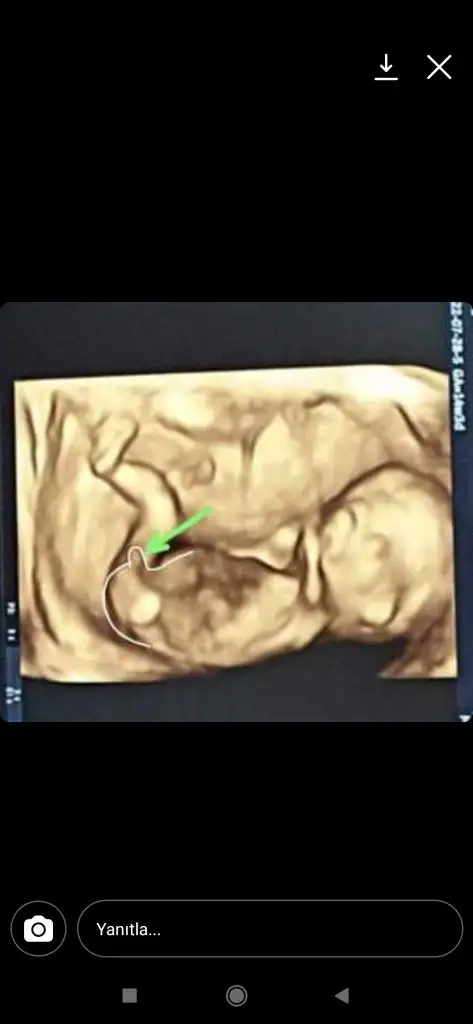

Ya bilmiyorum baba bnm ki erkek gibi geldi USG varmi sizinYa hayırlı olsun sağlıkla gelsin inşallahbanada erkek dedi çıkıntıyı gösterdi sonra usg resmi istedim bacak arası tekrar baktı çekti ama bakıyorum birşey görünmüyor acaba resimden mi öyle oldu anlamadım ama cinsiyete bakarken erkek dedi 15+3 haftalığız senin maşallah ne güzel çıkmış usg

Hangi sayfalara sordunuz ya happy mom neresiİnstgram da birkaç sayfaya sordum hepsi erkek dedi biri bile kız demedihappymom var uygulma oraya sordum tahminde bulunanlar 12 haftalıkta bacak arası dolu dediler çıkıntı dikmiş. Yarın netleşir inşallah sahabtan randevum var